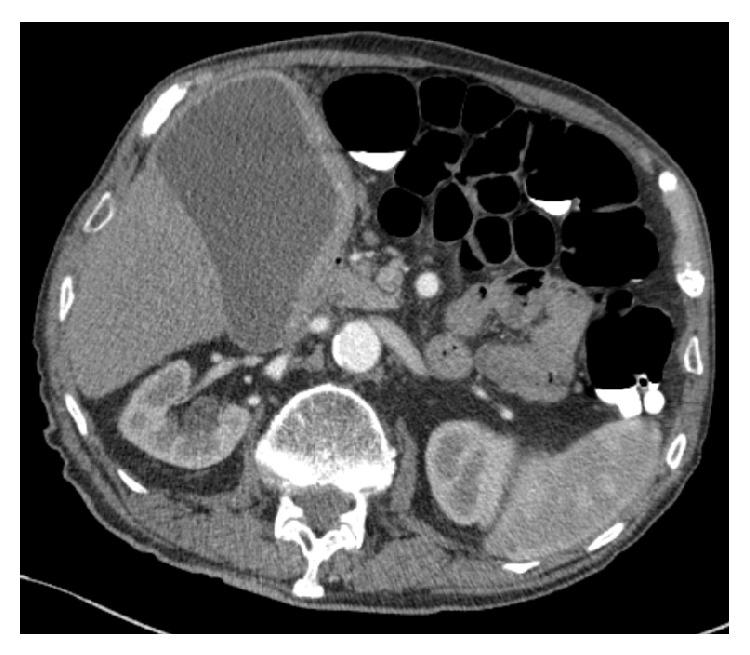

Primary malignant lymphoma of the gallbladder: a case report and literature review.

Br J Radiol. 2009 Jan;82(973):e15-9. doi: 10.1259/bjr/30768802.